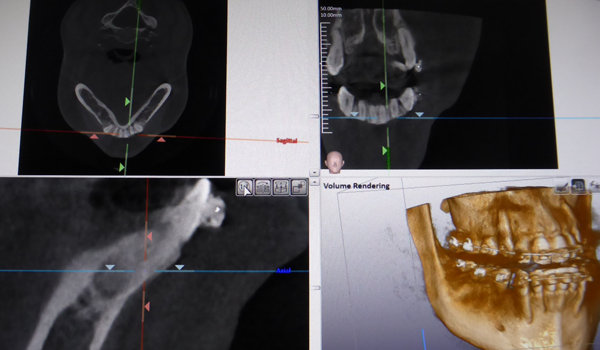

多くのインプラントは直径約4mm長さ10mmのチタン製のねじです。 このねじを完全に骨の中に入れることが長期にインプラントを機能させるために重要となります。

しかし歯周病などの原因で骨が少ないケースがあります。骨の量を確認するためにCTは必要となります。

下の奥歯にインプラント処置をする場合、下歯槽神経などの重要な神経を傷つけないために下歯槽管の位置を確認するために使用します。

上の奥歯にインプラント処置を行う場合 上顎洞と呼ばれる空洞の大きさや炎症の有無を調べるのに使用します。